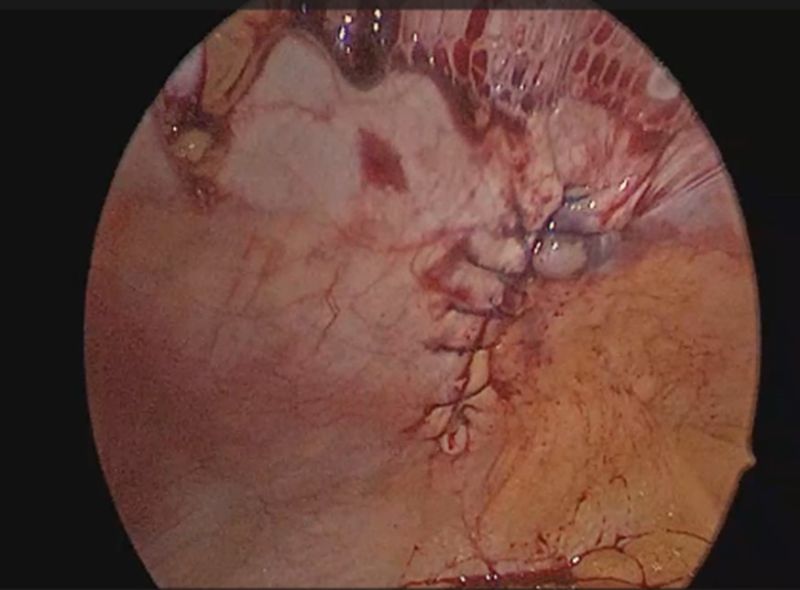

Plain CT scan of the abdomen was done that revealed a 3.1 cm sized defect in the anterior abdominal wall along the left lateral lumbar region with omentum and bowel loops as hernial contents. A diagnosis of trocar site incisional hernia (TSIH) was made, and the patient was planned for laparoscopic IPOM for the left lumbar hernia. Patient was placed in the supine position with a slight right tilt arms tucked by the side. Pneumoperitoneum was created using a Veress needle at the palmer’s point. Optical view entry using a 5mm optical trocar was done at the right hypochondrium, then a right iliac 5mm port and another 10mm port in the right lumbar region were placed under vision for instrumentation (figure 1). Adhesions were visualized over the previous mesh and adhesiolysis was performed. A defect in left lumbar region was seen, and it was approximated using absorbable barbed sutures in a continuous fashion. A 15x15 composite mesh was placed over the defect with a margin of 5 cm on either side. The defect was seen to be overlying on the previous mesh. Mesh was sutured using absorbable barbed sutures and inner crowning of the mesh was done using absorbable tacks. TAP block was given laparoscopically and proper haemostasis was achieved. 10mm port site was closed using a non-absorbable figure-of-8 stitch. Patient was shifted to ward, and she was managed with intravenous analgesics, antibiotics as well as antacids. Visual analogue scale (VAS) score for pain on post-operative day-1 was 3 out of 10. The patient recovered well after the procedure and was discharged in a hemodynamically stable state on post-operative day 2.

Figure 4: Defect closure with absorbable barbed continuous sutures